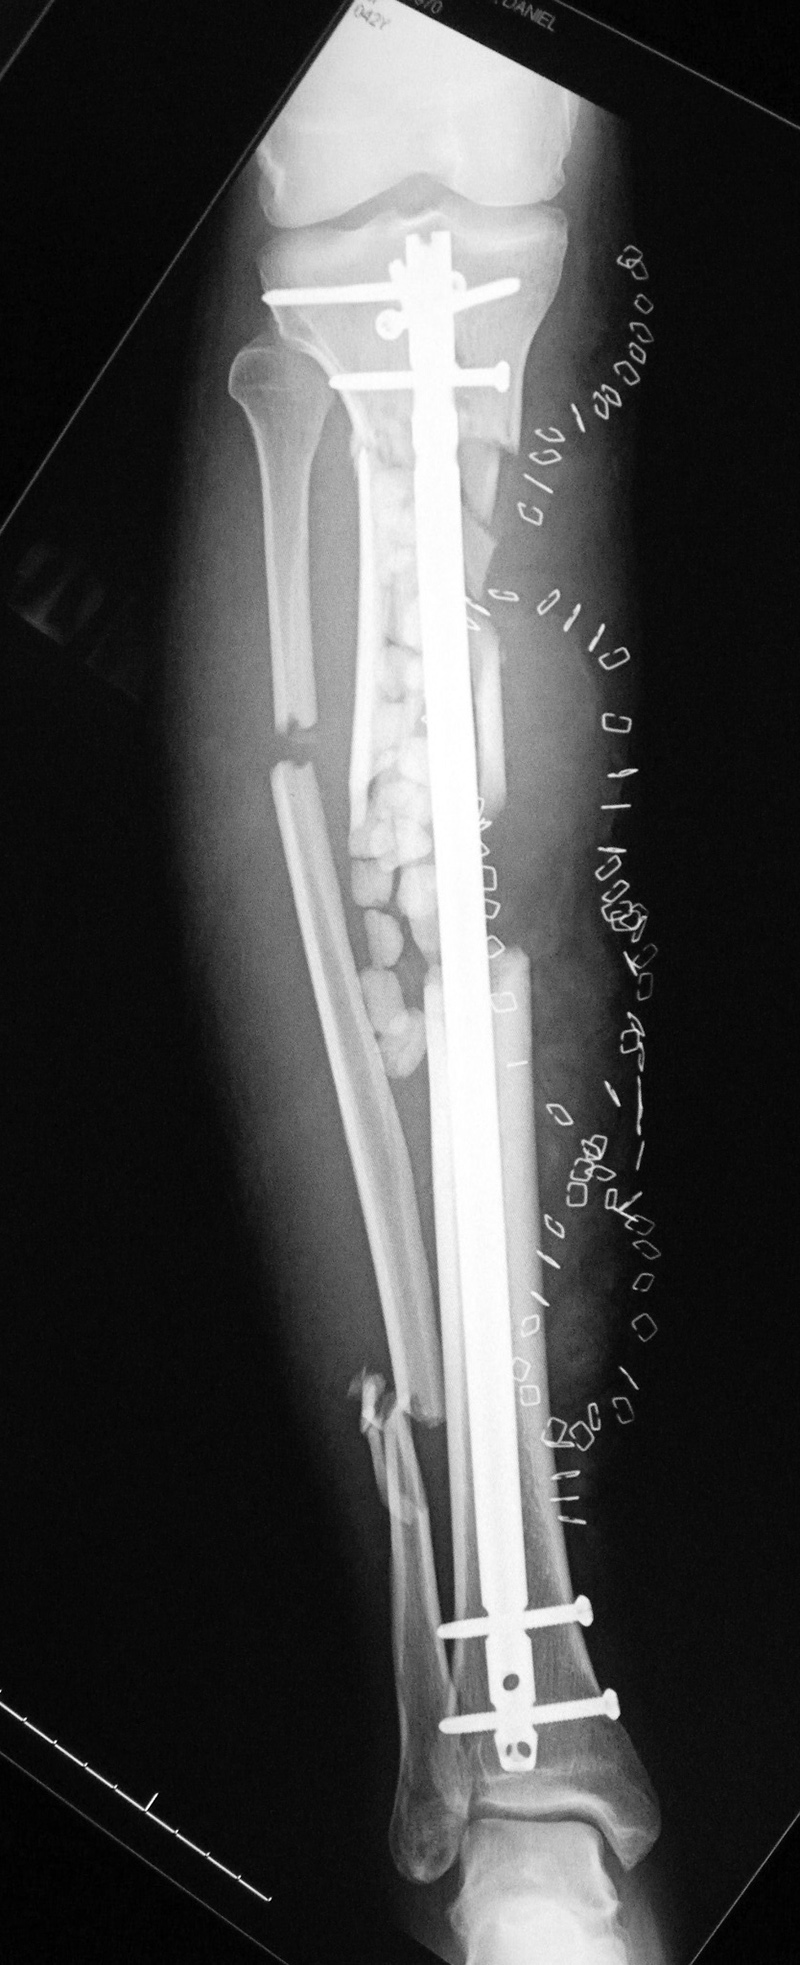

43 year-old man with comminuted right tibia and fibula fractures as well as extensive bone loss and soft tissue injury. A tibial intramedullary nail with proximal and distal locking screws is present as well as multiple rounded bony allografts. There are also large skin staples.